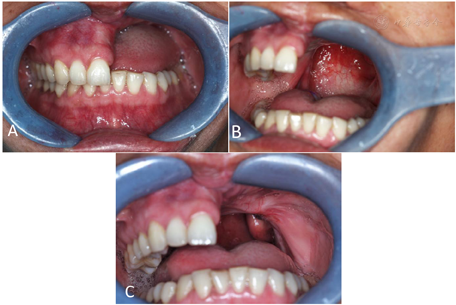

颌面部基本对称,开口约2横指,口内21~27缺失,左侧缺牙区牙槽骨、上颌骨缺失,左侧硬腭完全缺失,软腭完全缺失,口鼻相通。左颊、硬腭缺损处可见皮瓣修复,有瘢痕挛缩。构音不清,饮水时鼻漏(图4)。病理结果示:黏液表皮样癌。

治疗计划:拟行上颌阻塞器式活动义齿修复。治疗过程:(1)牙体预备,制备11~16舌侧导平面和小连接体空间,制备13、14和15、16和16、17间隙卡位置。(2)制取初次印模(同例1)。(3)试支架确定颌位关系,同期制取咽腔功能式印模(同例1)。(4)试戴。(5)充胶戴牙(图5)。